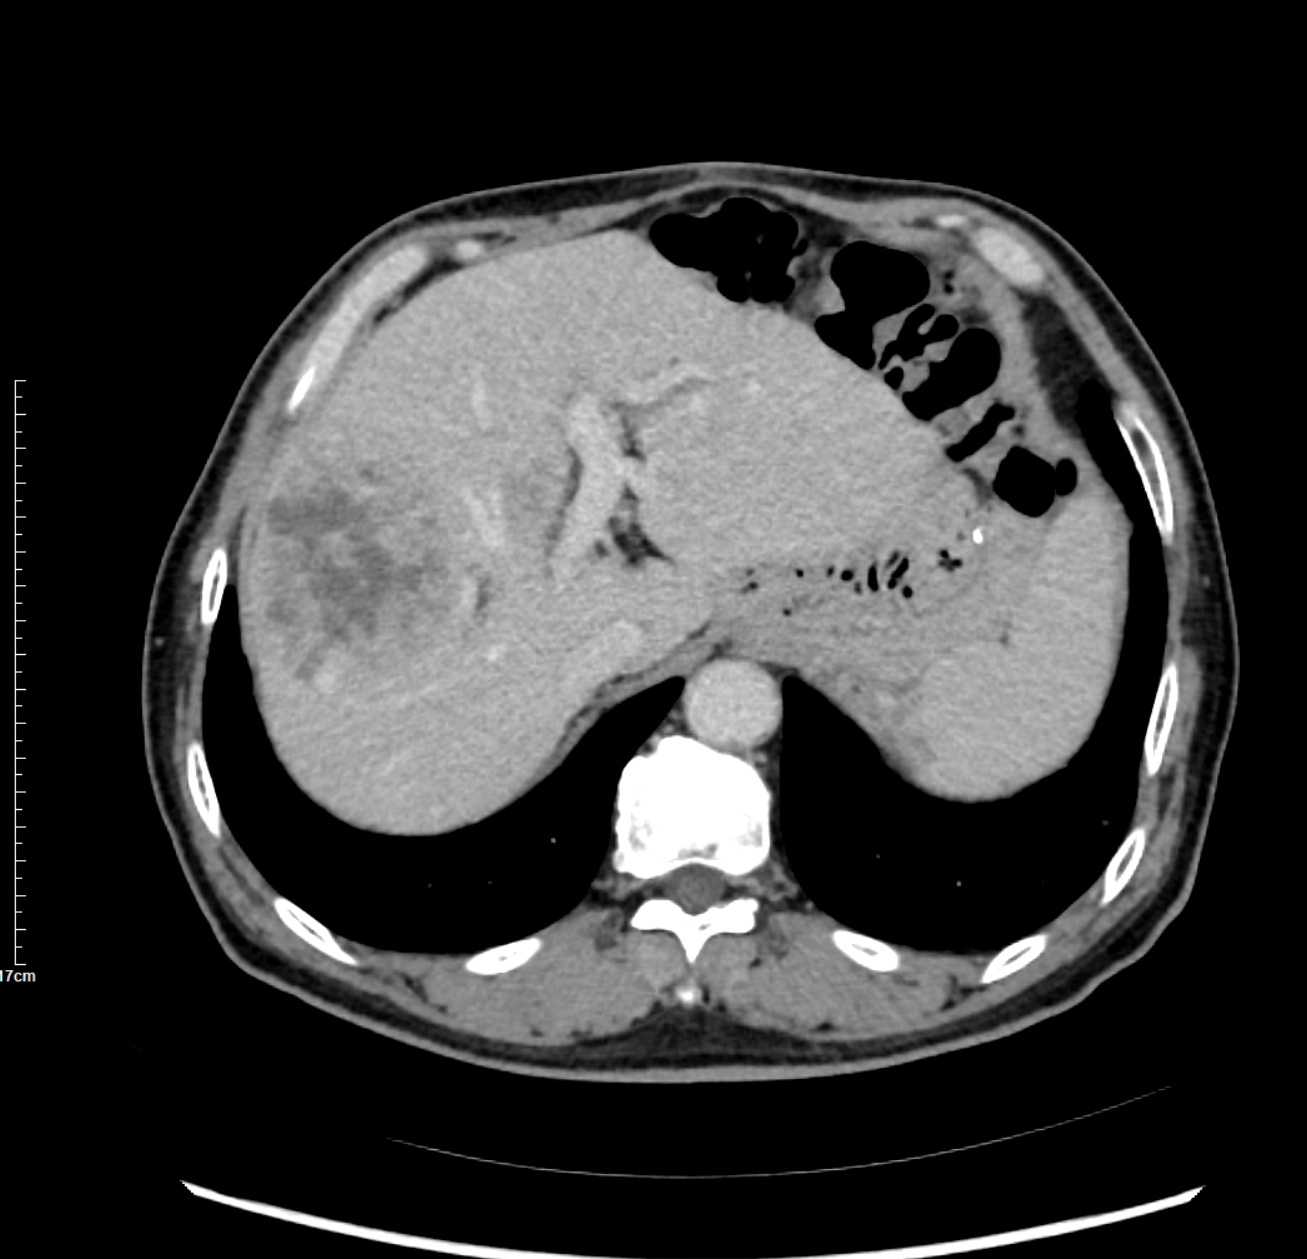

术前影像资料

皇家丽肝癌钇90多学科治疗专家团队由核医学科、微创介入科、肝胆外科、肿瘤外科等多个学科的专家组成。为确保患者治疗安全,曹明溶主任医师、牛惠敏主任医师、刘生主任医师等团队专家做了大量的调研,围绕患者的各项指标开展了多次多学科术前讨论,最终制定了治疗方案。患者术中全程意识清醒、生命体征平稳,目前恢复情况良好。